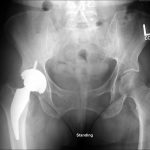

Pre-Op AP Pelvis

Harris Hip Score 48 (max=100) | Oxford Hip Score 19 (max=48)

6-Week Post-Op

Harris Hip Score 96 (max=100) | Oxford Hip Score 38 (max=48)